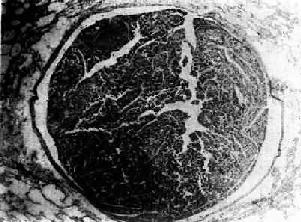

羊水栓塞(amniotic fluid embolism)是分娩过程中一种较罕见的疾患。在分娩过程中,如羊膜破裂,尤其又有胎儿头阻塞阴道口时,子宫收缩可将羊水压入破裂的子宫壁静脉窦内,羊水成分可由子宫静脉进入肺循环,在肺动脉分支及毛细血管内引起羊水栓塞。少量羊水可通过肺毛细血管进入大循环引起多数器官小血管的栓塞。镜下,羊水栓塞的证据是在小动脉和毛细血管内发现羊水成分:角化上皮,胎毛,胎脂,胎粪和粘液(图3-9)。本病发病急骤,产妇出现紫绀、呼吸困难和休克,绝大多数导致死亡。羊水成分栓塞肺血管所致的肺循环机械性阻塞,实不足以解释上述症状,因此过敏性休克、DIC、羊水液体内所含的血管活性物质进入血液引起血管反应可能是致死的原因。羊水具有凝血致活酶作用,可引起DIC,一些羊水栓塞病例,肺微血管内有纤维素性血栓存在。

图3-9 肺羊水栓塞

小血管内有角化上皮